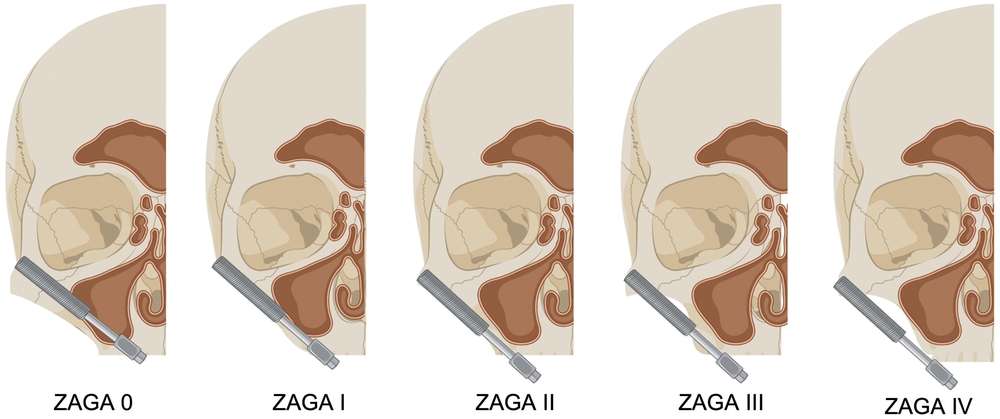

Um festzustellen, ob ein Patient mit atrophem Oberkiefer oder Oberkieferdefekt für die Versorgung mit Zygoma-Implantaten geeignet ist, sind vor allem dreidimensionale radiologische Untersuchungen notwendig. So wird eine minimale Dimension des Jochbeinkörpers von 7 mm empfohlen, um die Implantate apikal primärstabil verankern zu können. Zur weiteren Planung und Durchführung bietet sich der von der Zygomaanatomie geführte Zugang („Zygoma Anatomy Guided Approach“ - ZAGA) nach Aparicio an [Aparicio, 2011]. Jener beschreibt den Grad der Konkavität der lateralen Kieferhöhlenwand und den Grad der palatinalen Resorption des verbleibenden Kieferkamms.

Die ZAGA-Klassifizierung reicht von 0-4 (Abbildung 6). Der Zahnarzt importiert den 3-D-Scan des Patienten in eine Planungssoftware seiner Wahl (zum Beispiel coDiagnostiX®, Dental Wings GmbH, Chemnitz, Deutschland - Abbildung 7) und simuliert das Zygoma-Implantat an der gewünschten Position. Auf diese Weise kann er visualisieren und voraussagen, ob die Plattform des Zygoma-Implantats in der Maxilla des Patienten stabilisiert wird und ob der mittlere Teil des Zygoma-Implantats vollständig innerhalb, teilweise innerhalb oder vollständig außerhalb der Kieferhöhle liegt. Wie von Aparicio berichtet, hatten 93,5 Prozent der untersuchten Patienten eine ZAGA 0-3 Anatomie und nur 6,5 Prozent eine Topografie, die mit ZAGA 4 übereinstimmte [Aparicio, 2011].